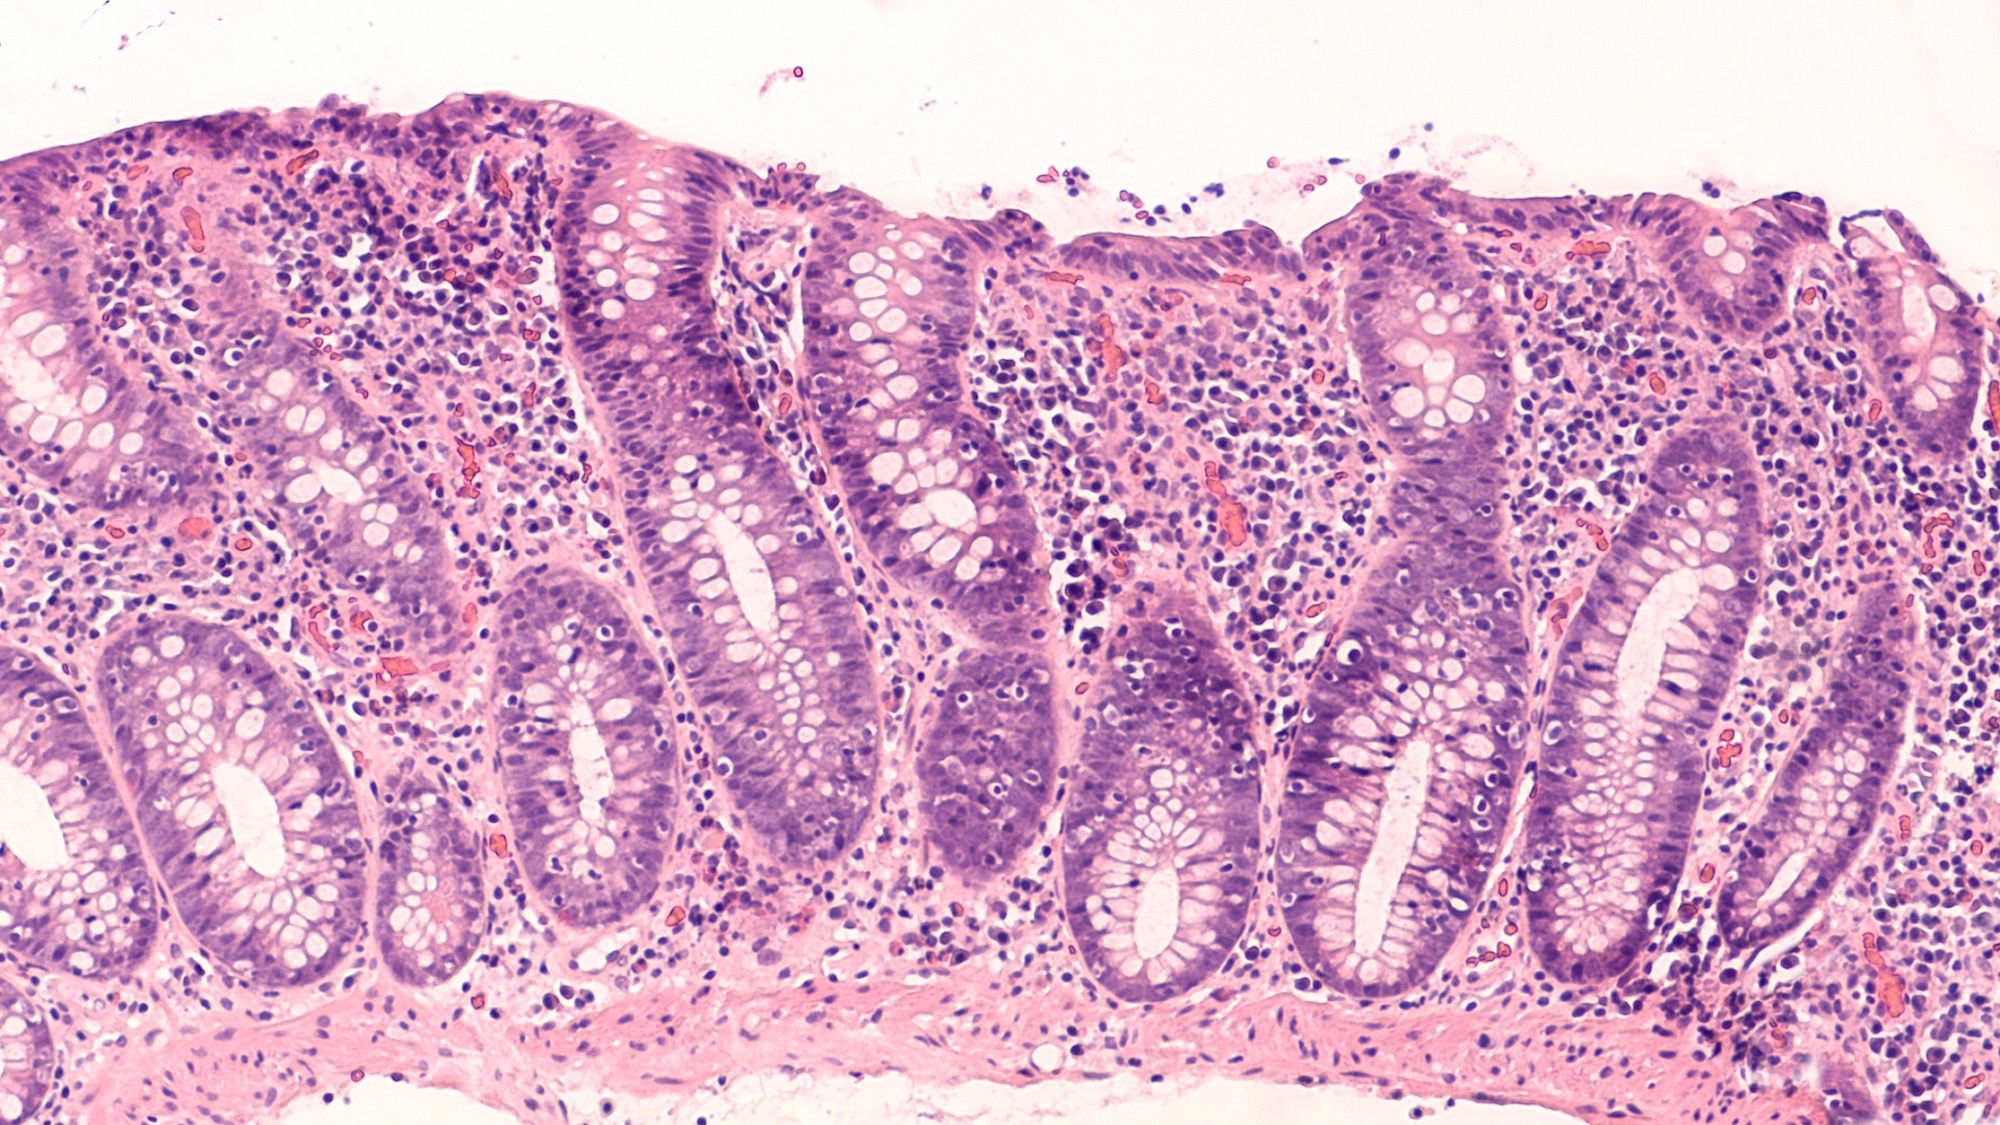

Photomicrograph of lymphocytic colitis, a type of microscopic colitis, showing increased numbers of intraepithelial lymphocytes Study: Inulin-Butyrate Nanogel for Modulation of Gut Microbiome, Intestinal Barrier, and Regulatory T-Cells in Colitis. Image Credit: David A Litman/Shutterstock.com

Therapeutically, IBN outperformed inulin or butyrate alone across several readouts. Treated mice lost less body weight, retained more colon length, and showed lower inflammatory burden. Histological analysis also found less epithelial injury and reduced immune cell infiltration.